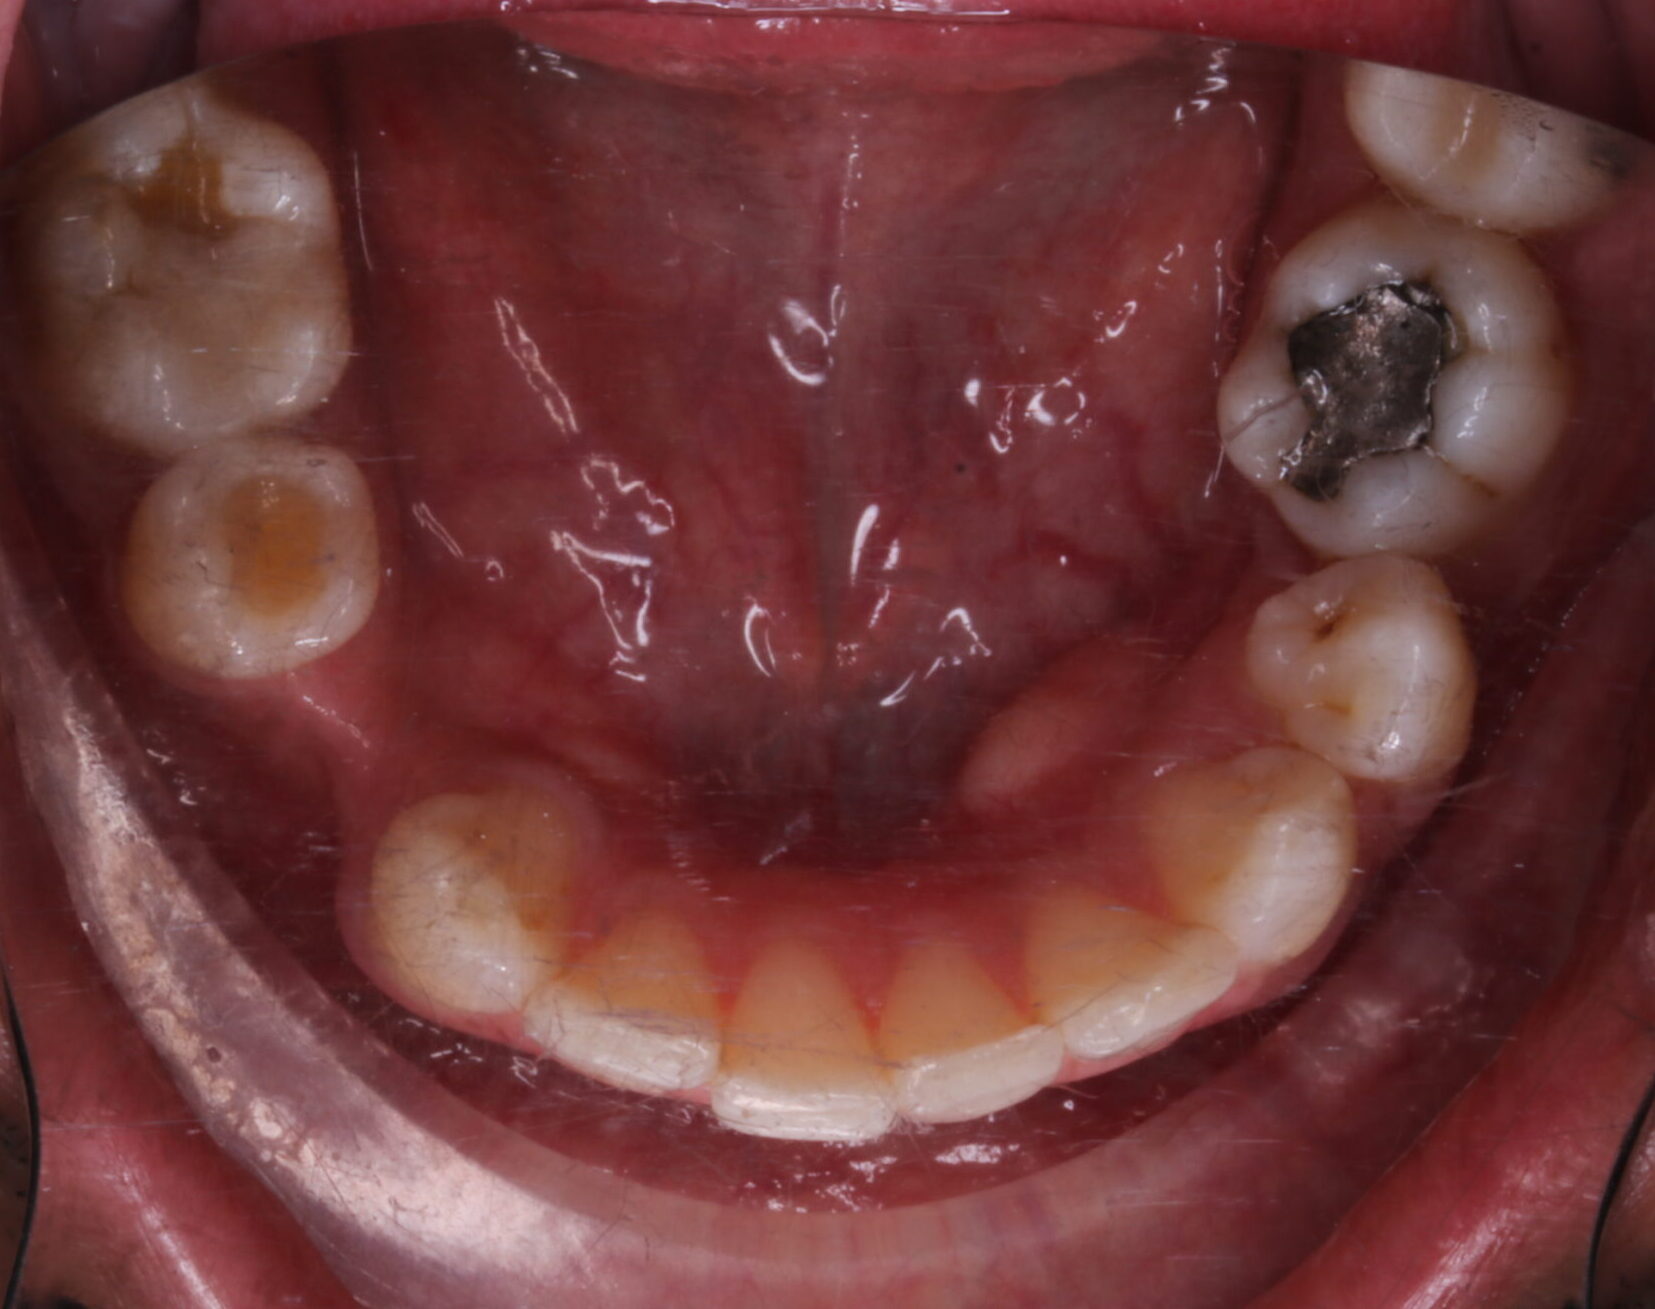

PÉRDIDA ÓSEA GENERALIZADA EN MANDÍBULA ( ORTOPANTOMOGRAFÍA);EXODONCIA DE 18

FOTOGRAFÍAS DE INTERÉS